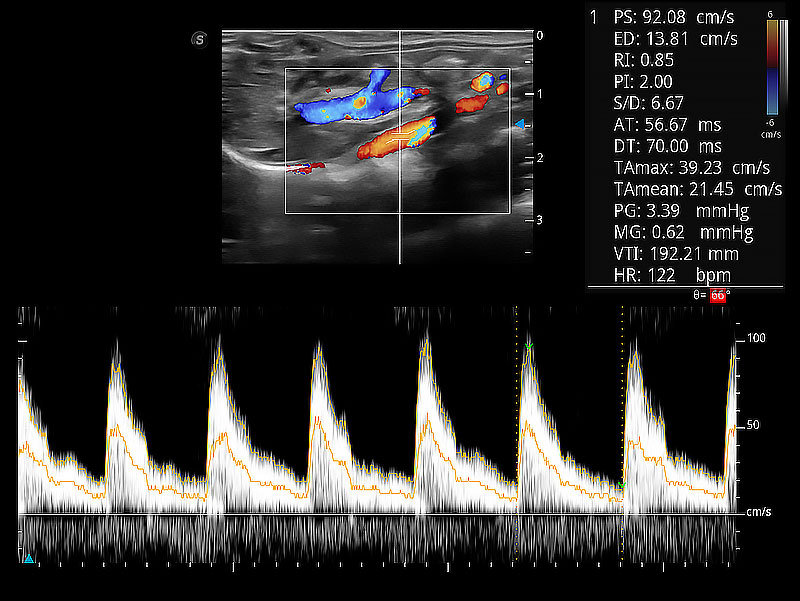

極大提升超低速微細血流的檢出能力,同時更精準地濾除軟組織和超聲信號,為獸用醫(yī)生提供以往無法通過常規(guī)血流獲得的疾病診斷信息。

在傳統(tǒng)二維血流成像的基礎上,呈現(xiàn)血流的立體感,具有動感的生命力之美。即便是微小的血管也能輕松應對,提高了血流的視覺敏感性。

隨著取樣門位置改變,頻譜多普勒包絡可進行自動眼蹤測量,且可自由配置測量的參數(shù)。